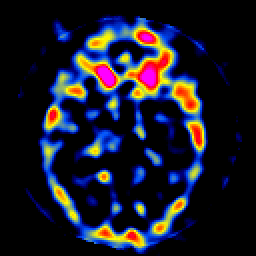

SPECT TL Study #8 -- Slice #22

[Home][Help][Clinical][Tour 1][Tour 2][Tour 3] Slice 22